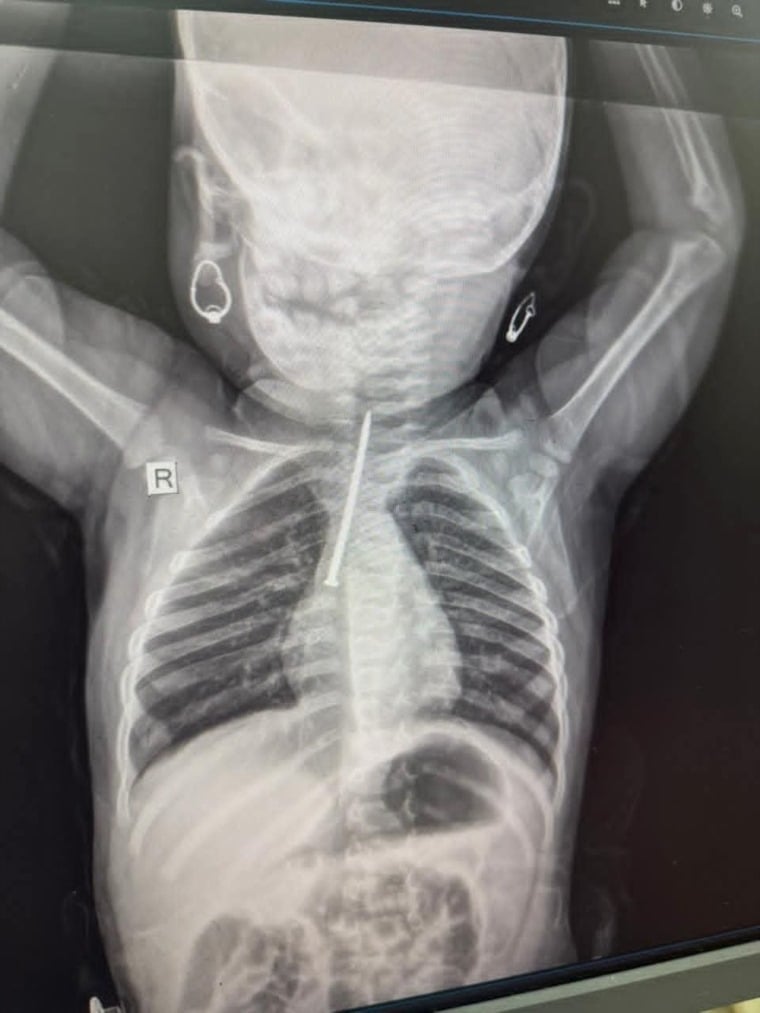

مدار الساعة-دخلت طفلة تبلغ من العمر عشرة أشهر إلى مستشفى السلام في الموصل بعد أن ابتلعت جسماً غريباً استقر في قصبتها الهوائية.

وتمكن فريق طبي بقيادة الدكتور محمد سالم المشهداني، اختصاصي جراحة الصدر والقلب والأوعية الدموية في محافظة نينوى، من إزالة مسمار طويل باستخدام منظار القصبات الهوائية، في عملية دقيقة أُجريت عند الساعة الحادية عشر ليلاً.وأوضحت إدارة المستشفى أن التدخل المبكر أسهم في منع أي مضاعفات تهدد حياة الطفلة، مشددة على أهمية توعية الأهالي بمخاطر الأجسام الصغيرة التي قد يضعها الأطفال في أفواههم أو يبتلعونها عن طريق الخطأ.وأكدت المستشفى أن الإجراءات الطبية مجهزة للتعامل مع الحالات الطارئة من هذا النوع، وأن التدريب المستمر للطواقم الطبية يضمن تنفيذ العمليات بأعلى مستويات الدقة والسلامة. كما نبهت إلى ضرورة متابعة الأطفال باستمرار، خاصة في عمر أقل من سنتين، حيث تكون مخاطر ابتلاع الأجسام الصغيرة مرتفعة للغاية.العراق: إنقاذ حياة رضيعة بعد ابتلاعها مسماراً طويلاً اخترق قصبتها الهوائية